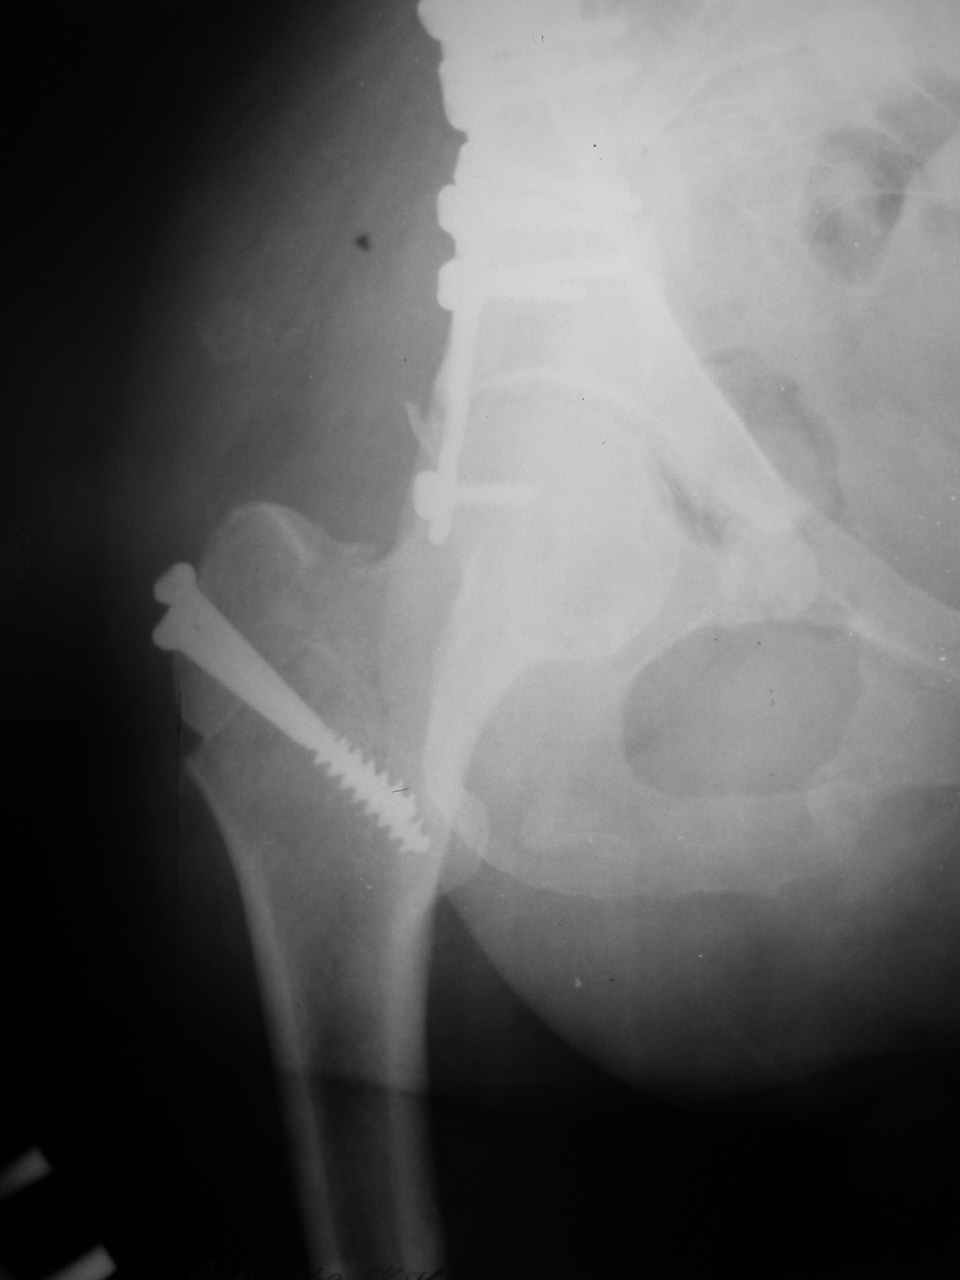

Re: Перелом вертлужной впадины

Снимки и схема